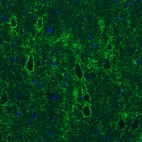

Immunohistochemical staining of rat globus pallidus shows strong immunoreactivity in GABAergic neural fibers.